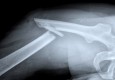

Tjeskoba slabi kosti

Pripazite - tjeskoba ima širi utjecaj na zdravlje nego što se do sada mislilo. Naime, ona može oslabjeti kosti. U to uvjeravaju stručnjaci iz Sveučilišta Deakin iz Australije i s nekoliko norveških sveučilišta koji su analizirali podatke preko 8.000 muškaraca…